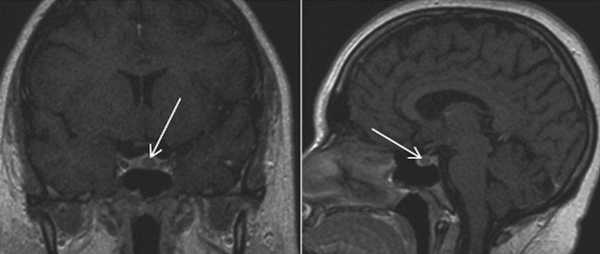

МРТ гипофиза с контрастом и без: А- гипофиз нормальных размеров (обведено кругом), В - симметричные кальцификации (стрелки)

Микроаденома гипофиза (указана стрелкой) на снимке МРТ

Поскольку диагностировать микроаденому по клиническим симптомам сложно, ее визуализация возможна только с помощью магнитно-резонансной томографии. Признаками микроаденомы на МРТ станут:

- При нативном сканировании в отделах аденогипофиза определяется зона гипоинтенсивного МР-сигнала на Т1-ВИ, округлой формы, с четкими, неровными контурами.

- После внутривенного введения парамагнитного контрастного препарата контрастное усиление выражено неравномерно, определяется равномерное накопление контрастного препарата неизмененной тканью гипофиза с задержкой контрастирования от выявленного участка в аденогипофизе.